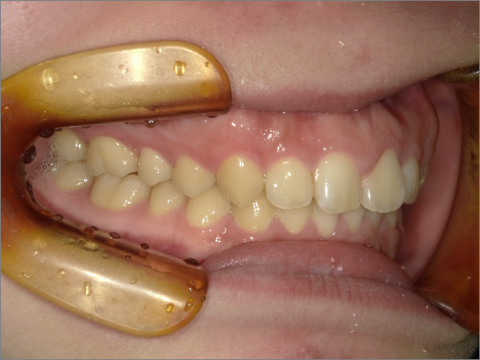

ご年齢 35歳男性

治療期間 2022/08/22〜2023/03/24(1年5ヶ月)

診断 110,000円(税込)

アライナー 550,000円(税込)

リテーナー 55,000円(税込)

BEFORE

AFTER